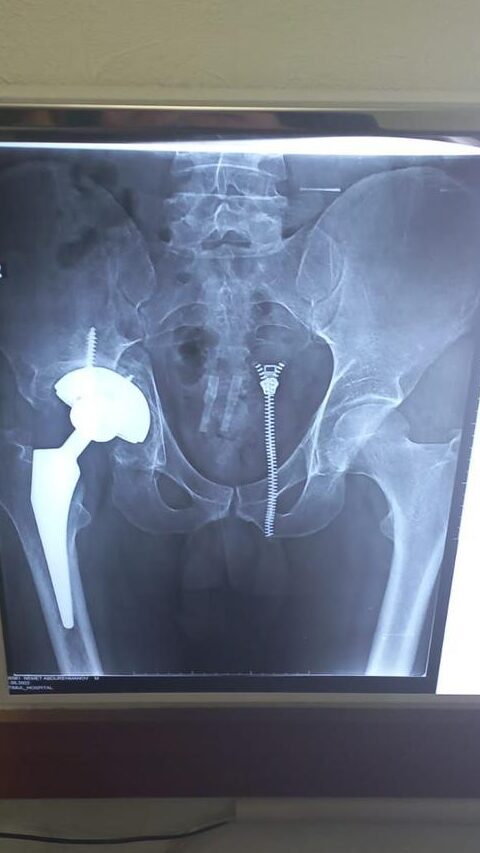

Bədənim dəfələrlə qırıldı,

çanağıma, çənəmə protezlər qoyuldu,

ayağıma millər yerləşdirildi…